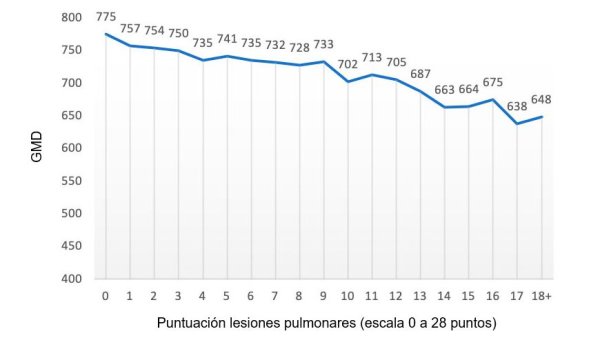

¿Cuál es el efecto real de las neumonías sobre el rendimiento económico de la explotación? ¿qué parecido hay entre una neumonía y el estrés por calor?